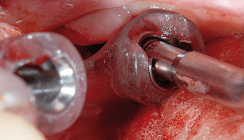

Wegen des Allgemeinzustandes der betagten Patientin wurde nach Rücksprache mit dem behandelnden Internisten die extraorale Implantatentfernung in Lokalanästhesie mit Sedierung und perioperativem Monitoring durch einen Internisten empfohlen. Die Antikoagulation sollte nicht unterbrochen werden. Die chirurgische Entfernung der gelockerten Implantate wurde unter antibiotischer Abschirmung (1,5 g Spizef i. v.) von einem extraoralen Zugang durch die submandibulär gelegene Narbe vorgenommen (Abb. 12). Die Schraubenköpfe der Implantate 32 und 41 waren von kallösem Knochengewebe überwachsen. Nach dessen Entfernung ließen sich die instabilen Schrauben problemlos herausdrehen (Abb. 13). Die Wunde wurde, insbesondere wegen der durch die Antikoagulation bestehenden Blutungsproblematik sowohl extraoral als auch intraoral dicht verschlossen.

Da ein ausreichender Prothesenhalt ohne Fixierung durch Implantate zukünftig nicht möglich gewesen wäre, andererseits sich konventionelle präprothetisch-chirurgische Eingriffe wie eine Vestibulumplastik oder eine Augmentation des atrophierten Alveolarkamms wegen der allgemeinmedizinischen Problematik verbaten, wurden in derselben Sitzung durchmesserreduzierte Titanschraubenimplantate (Straumann Roxolid RN 3,3 mm) Regio 31 und 33 (Abb. 14) minimalinvasiv („flapless“) inseriert. Dadurch konnte das Nachblutungsrisiko reduziert werden. Die vorhandene Prothese wurde ausgeschliffen, weichbleibend unterfüttert und als Verbandplatte eingegliedert, die Patientin wegen der allgemeinmedizinischen Problematik und der Antikoagulation kurzstationär aufgenommen.